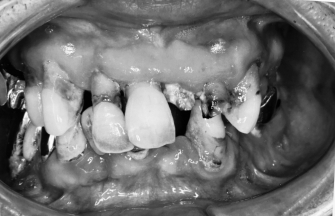

◎左写真 初診時

歯を治療したいと来院されました。

まずは基本となる歯周病の治療を行い、

その後虫歯の治療を行いました。

奥歯はすでに抜いている歯もありましたので

奥歯は入れ歯になりましたが、